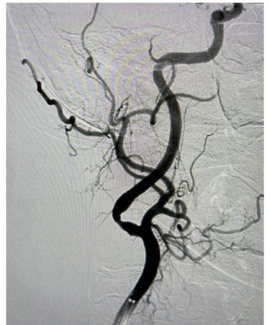

This case illustrates the potential for complications when facing severely fibrotic lesions in carotid catheterization.